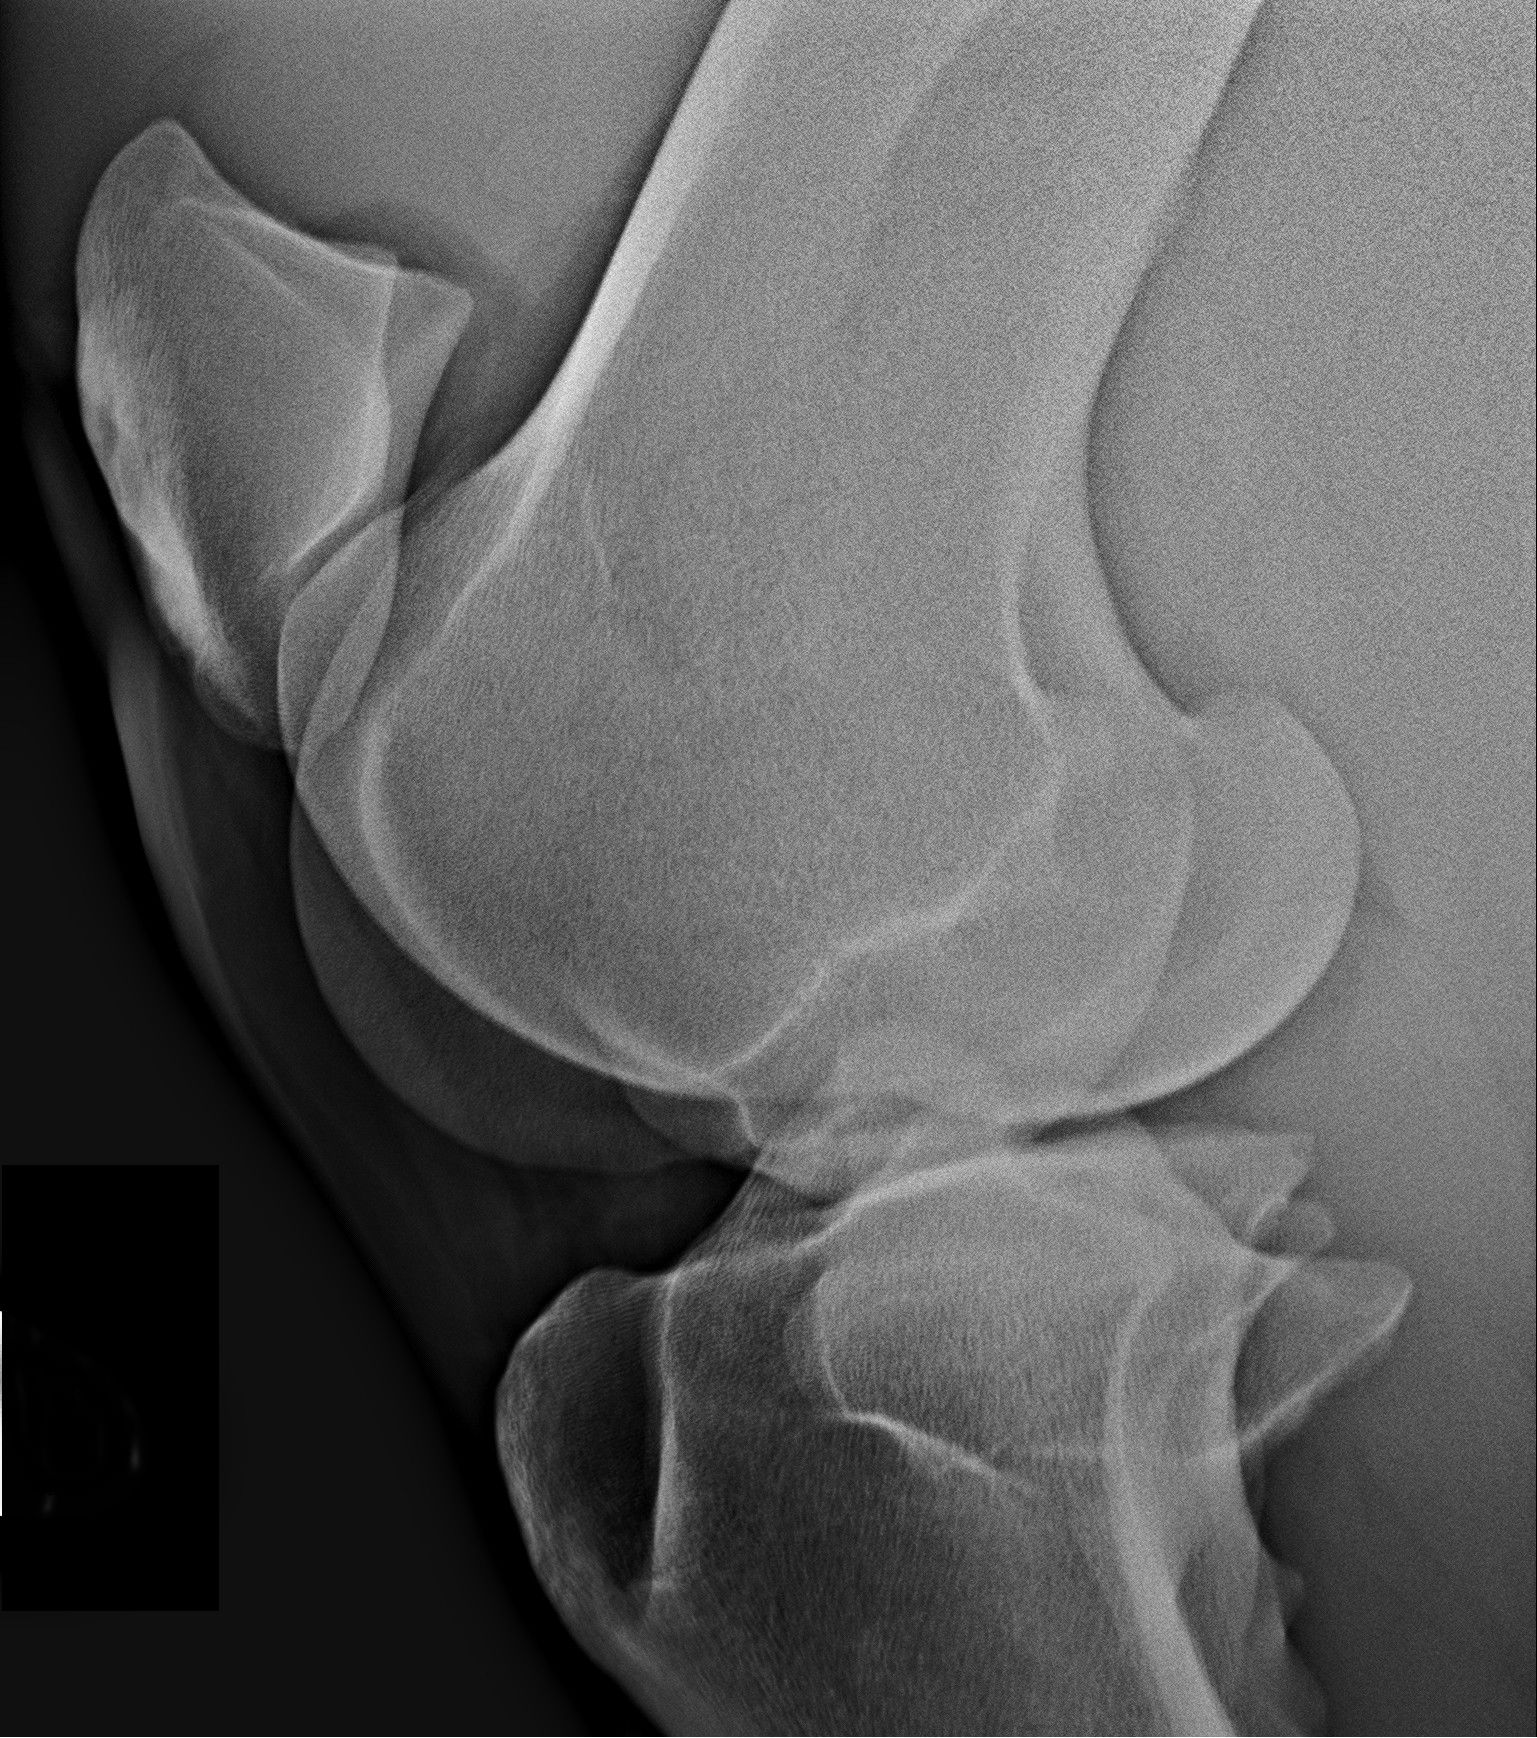

Így néz ki egy egészséges térd RTG felvétele: